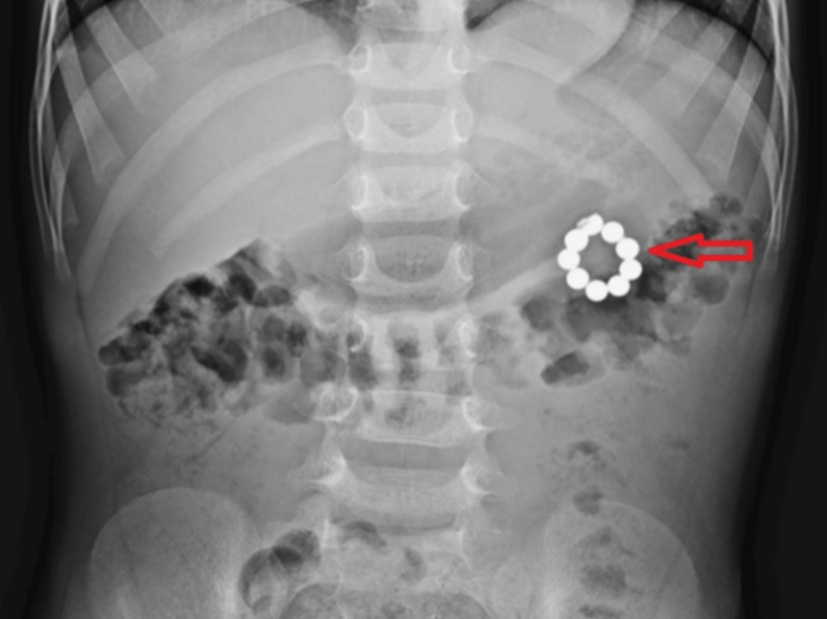

의료진에 따르면 아이는 3일간 복통과 메스꺼움 등을 겪다가 병원에 방문했다. 복부 엑스레이 촬영 결과, 아이의 뱃속에 여러 개의 구슬이 연결된 모양의 이물질이 관찰됐다.

아이의 장난감 상자에서 비슷한 모양의 구슬이 발견됐다. 아이가 삼킨 것은 '자석 팔찌' 일부인 것으로 확인됐다. 의료진은 내시경으로 위 안에서 구슬 5개를 꺼냈으나 남은 4개를 제거하지 못해 응급 개복 수술을 진행했다.